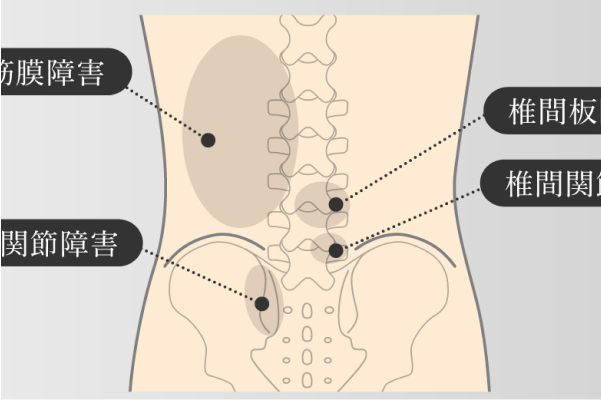

腰痛の原因ごとに施術を行っています。

椎間板性腰痛 / 椎間関節性腰痛 / 筋筋膜性腰痛 / いわゆるギックリ腰 / 脊柱管狭窄症 / 産前・産後の痛み